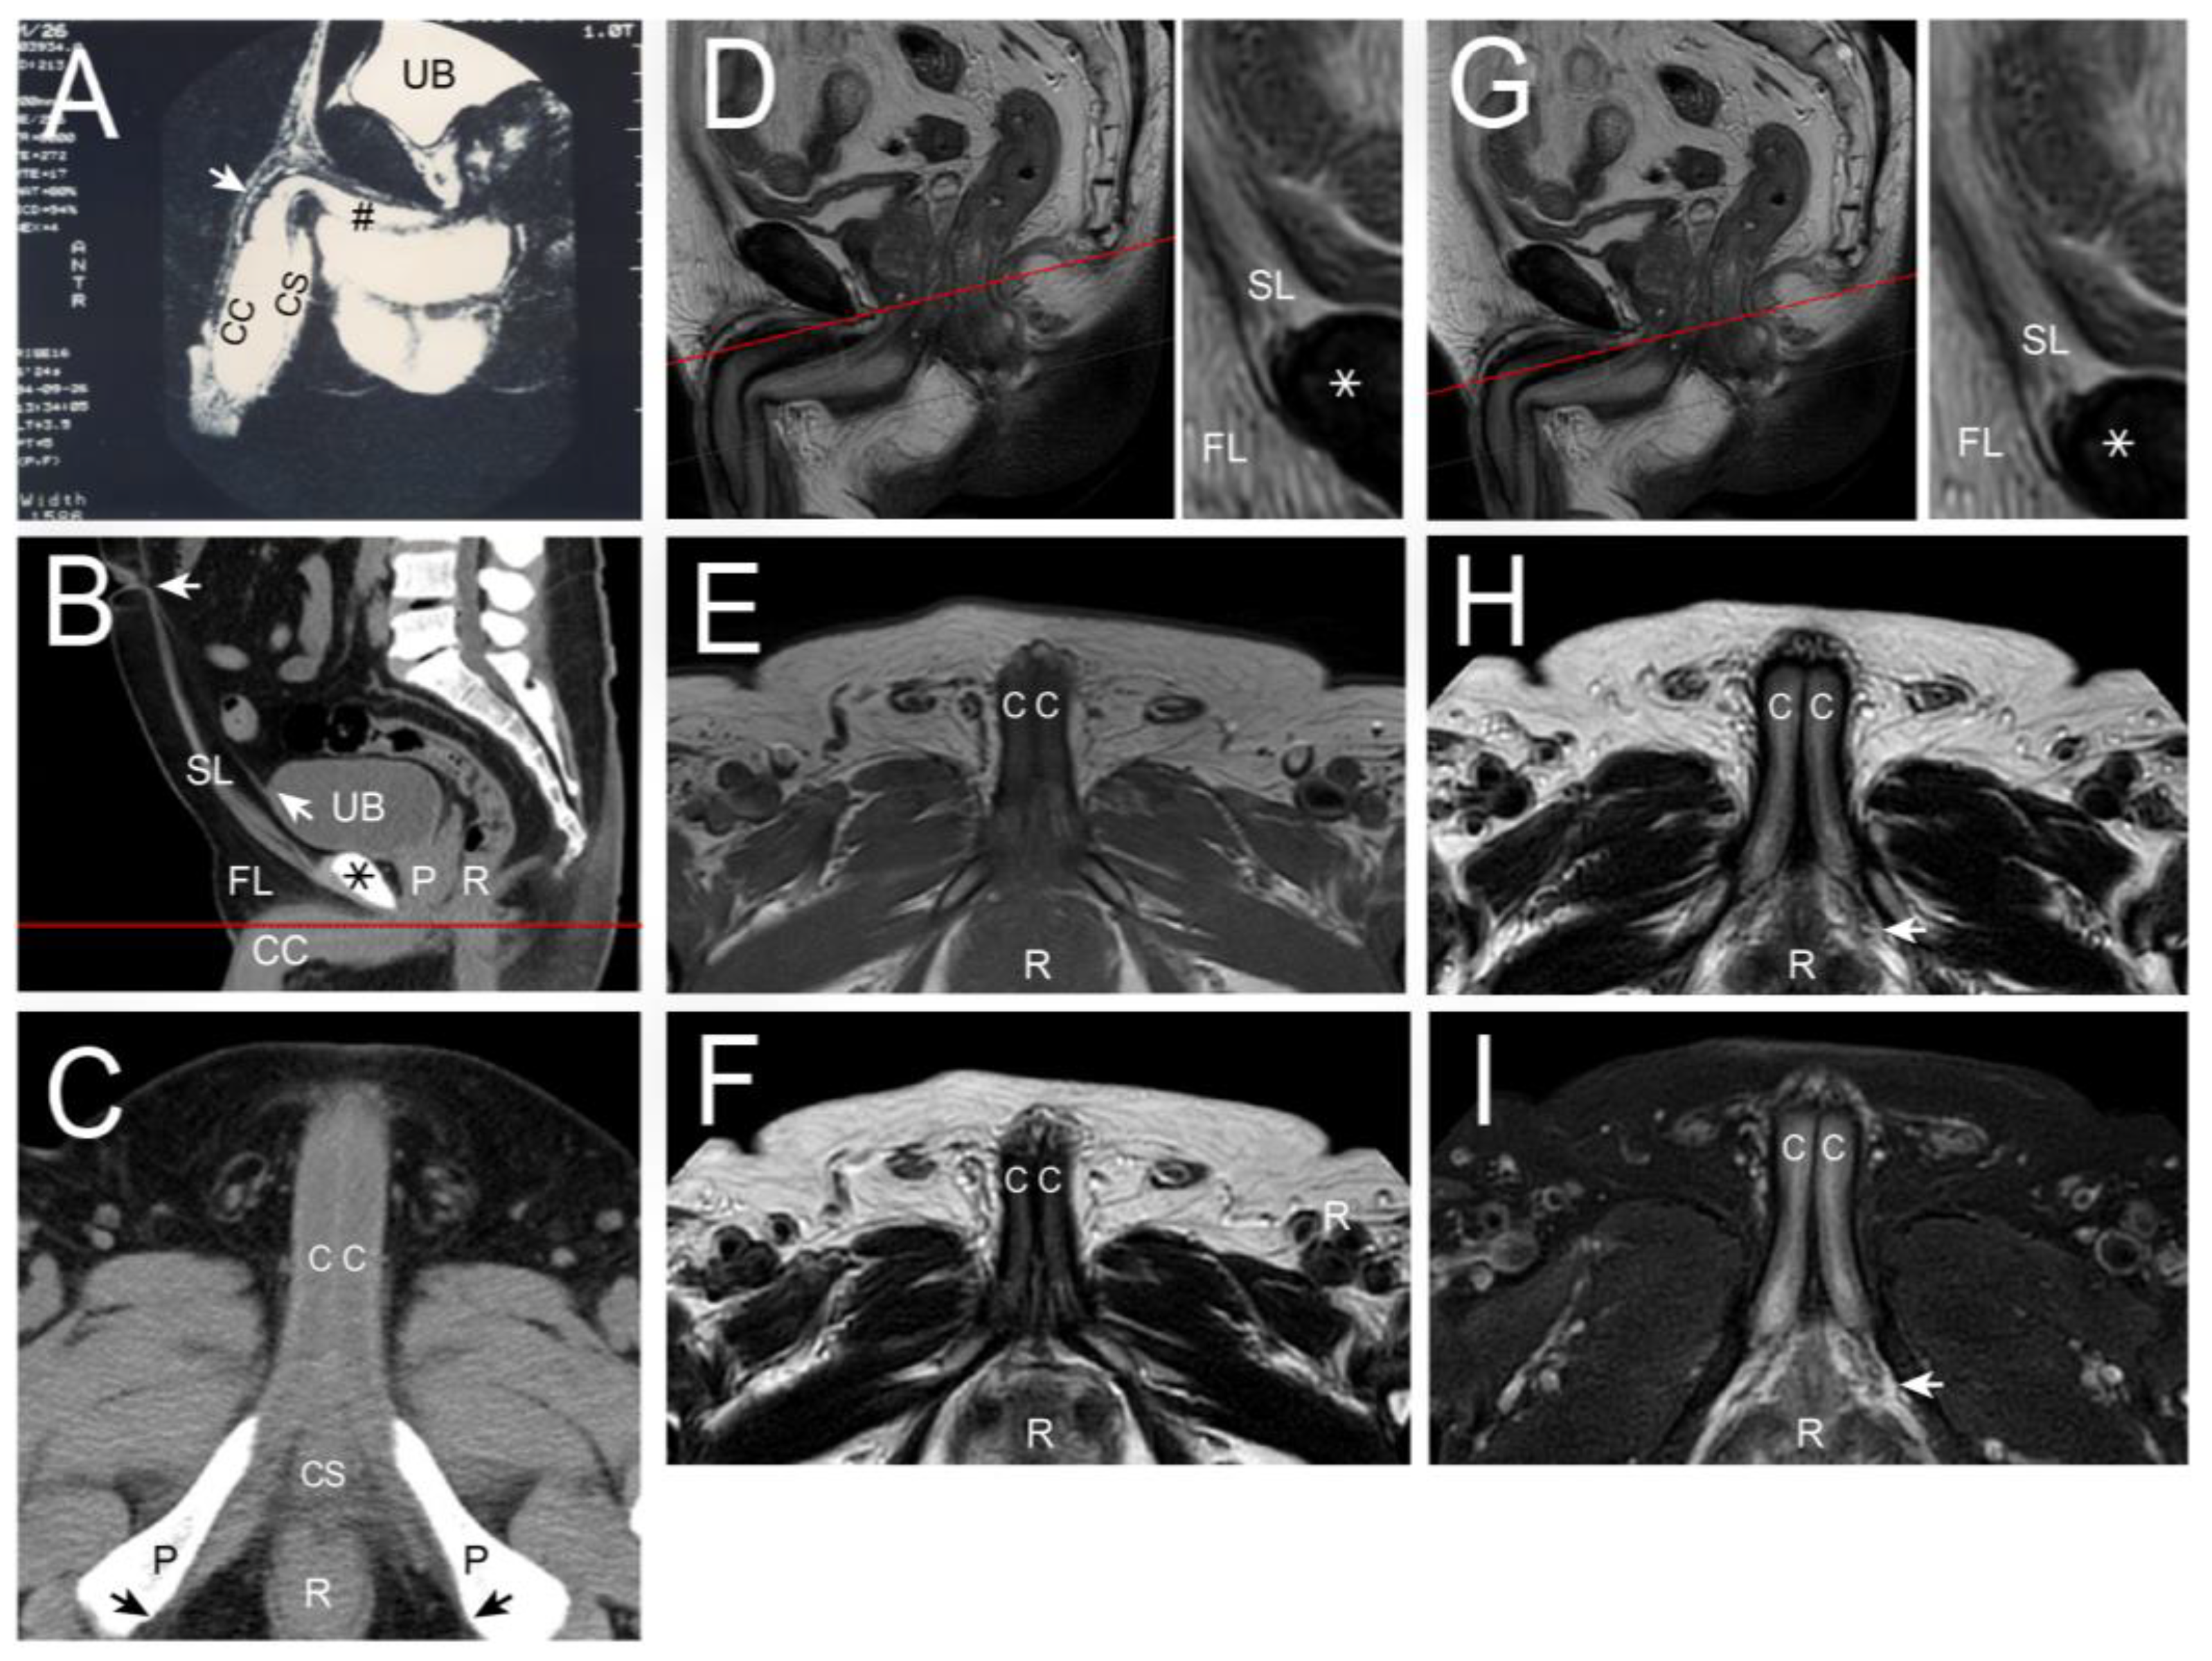

- Hsu, G.L.; Hill, J.W.; Chen, H.S.; Huang, S.-J. Novel pilot films providing indispensable information in pharmaco-cavernosography. Transl. Androl. Urol. 2014, 4, 398–405. [Google Scholar]

- Ghafoori, M. CT Cavernosography: A New Method for Evaluating venous Incompetence in Impotent Patients. Indian J. Radiol. 2010, 7, e78769. [Google Scholar]

- Kurbatov, D.G.; Kuznetsky, Y.Y.; Kitaev, S.V.; Brusensky, V.A. Magnetic resonance imaging as a potential tool for objective visualization of venous leakage in patients with veno-occlusive erectile dysfunction. Int. J. Impot. Res. 2008, 20, 192–198. [Google Scholar] [CrossRef] [PubMed][Green Version]